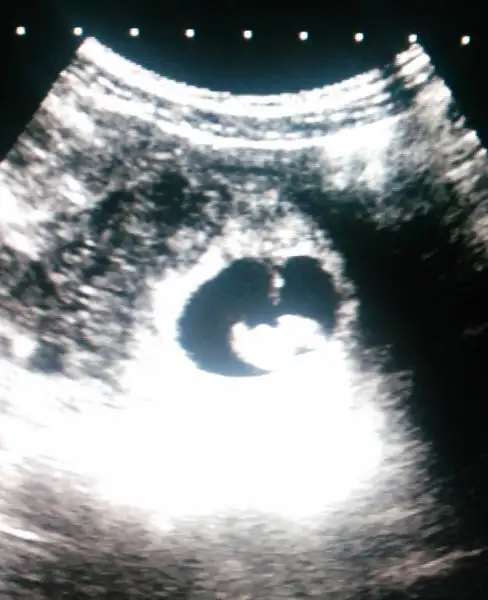

Hadi gözün aydın tatlım çok sevindim. Ben de cumartesi günü gittim kalbini dinledim 6+6 dedi doktor bana da. O zaman senin doğum tarihin de 24'ü değil değişecek. Seninle aramızda 2 gün görünüyor söylediğine göre.ayy kuzum gittim cumartesi doktora Rabbim' e şükürler olsun kalp atışını duyduk ve gördük 7+1 mişiz bir sıkıntı yok dedi şükürler olsun minnoşumu gördüm ölcektim heyecandan

Benim de 29'u görünüyor canım :)ultrason kağıdımda 27.10.2017 görünüyor canım tahmini doğum tarihi

Canm bnm en son gittiğimde 8+5 dim ama 8+1 gözüküyordm daha önce 6 gün geri idik 4 e düsmstü o kontrolde doktor da dediki bu ara kapanr hatta öne bile geçebilir ddi bnce sn son adetine Gore hesapla bn anneme de sordm tecrübe sonuçta 6 çocuk :)) 5 i sağ :) oda dedi ki adet den hesaplayıp erkekse ekimn ilk haftası doğar kızsa biraz erken doğabilir eylül sonu gbi dedi :) 40 hfta zaten 07 ekimde doluyor kadının hesabi doğru yani 38.hafta sonrası heran dogabilirler norml olursa :))Benim de 29'u görünüyor canım :)